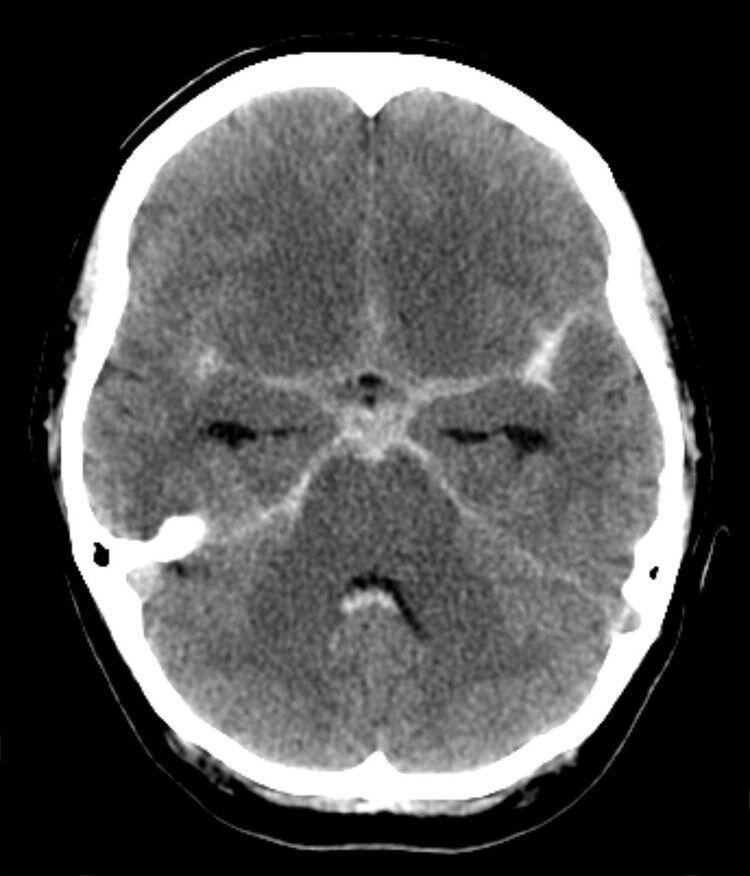

X-RAY QUIZ: Which finding is present on this image?

B: Sail sign

C: Meniscus sign